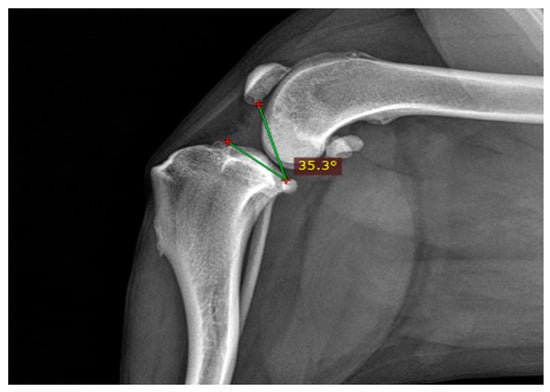

- Lorinson, K.; Kneissl, S.; Tichy, A.; Lorinson, D. Radiographic Measurement of the Patellar Height in Cats Using the Tibia Plateau-Patella Angle (TPPA). Biomed. J. Sci. Tech. Res. 2023, 49, 40929–40933. [Google Scholar]